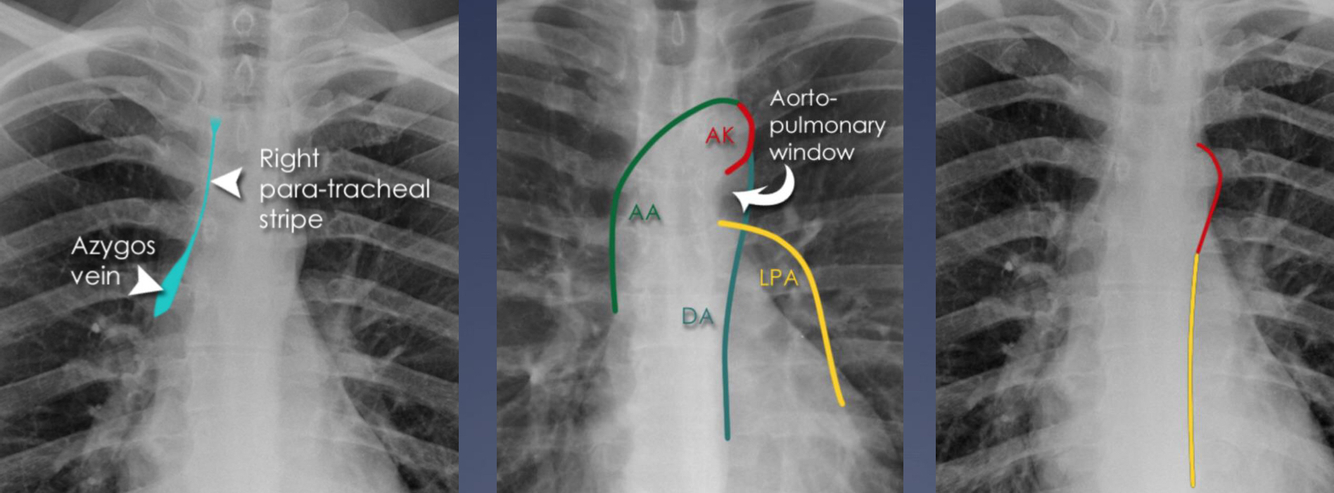

What contours should you see at the mediastinum, e.g aortic knuckle?

Aortic window and LPA disappear with enlarged lymph node